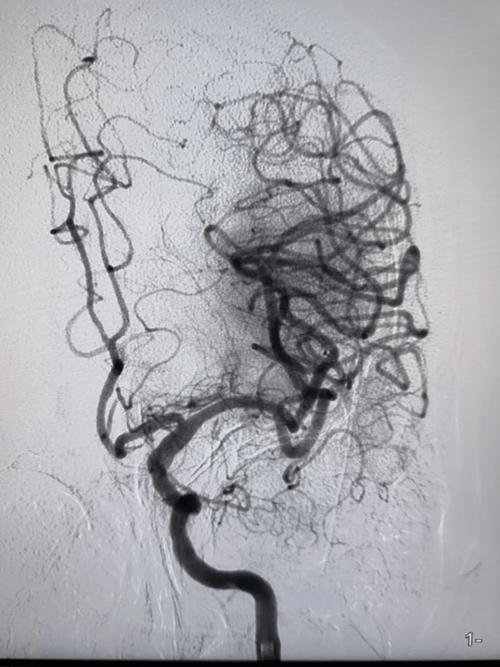

解密心脏CTA:看清“心脑动脉”的“路况”

心脏CTA(Computed Tomography Angiography),全称“冠状动脉CT血管成像”, 是一种无创、高效的检查方法,它通过静脉注射造影剂,利用多层螺旋CT对心脏冠状动脉及其主要分支进行三维成像,能够清晰显示血管的狭窄、斑块、畸形等情况。